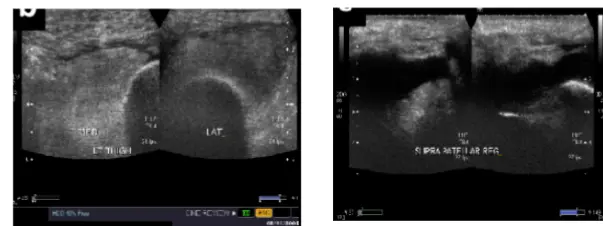

| Effusion: Milking OR Patellar Tap | Detect presence and severity of joint fluid | Large Effusion visible: Patellar Tap (Balloting): ![]() | Minimal effusion: Fluid demonstrable with “milking.” Mild effusion: Fluid pushed away, then reappears. Moderate effusion: Fluid not pushed away. Moderate/severe effusion: Positive patellar tap (balloting). | |